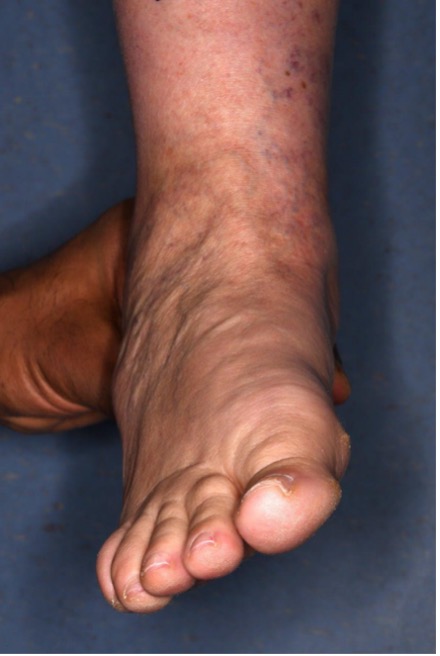

Figure 6. "Too many toes" sign; bilateral pathology (left side worse)

Figure 7: Standing AP, oblique and lateral showing talar head uncovering and loss of Meary’s angle (J&S Stage IIA disease)

Figure 8: Standing AP and lateral showing bilateral talar head uncovering and loss of Meary’s angle (J&S Stage IIB disease)